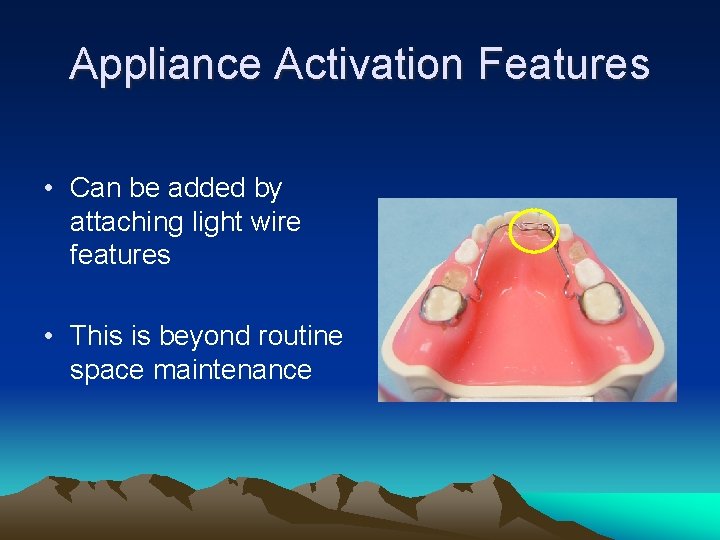

Appliance Activation Features • Can be added by attaching light wire features • This is beyond routine space maintenance